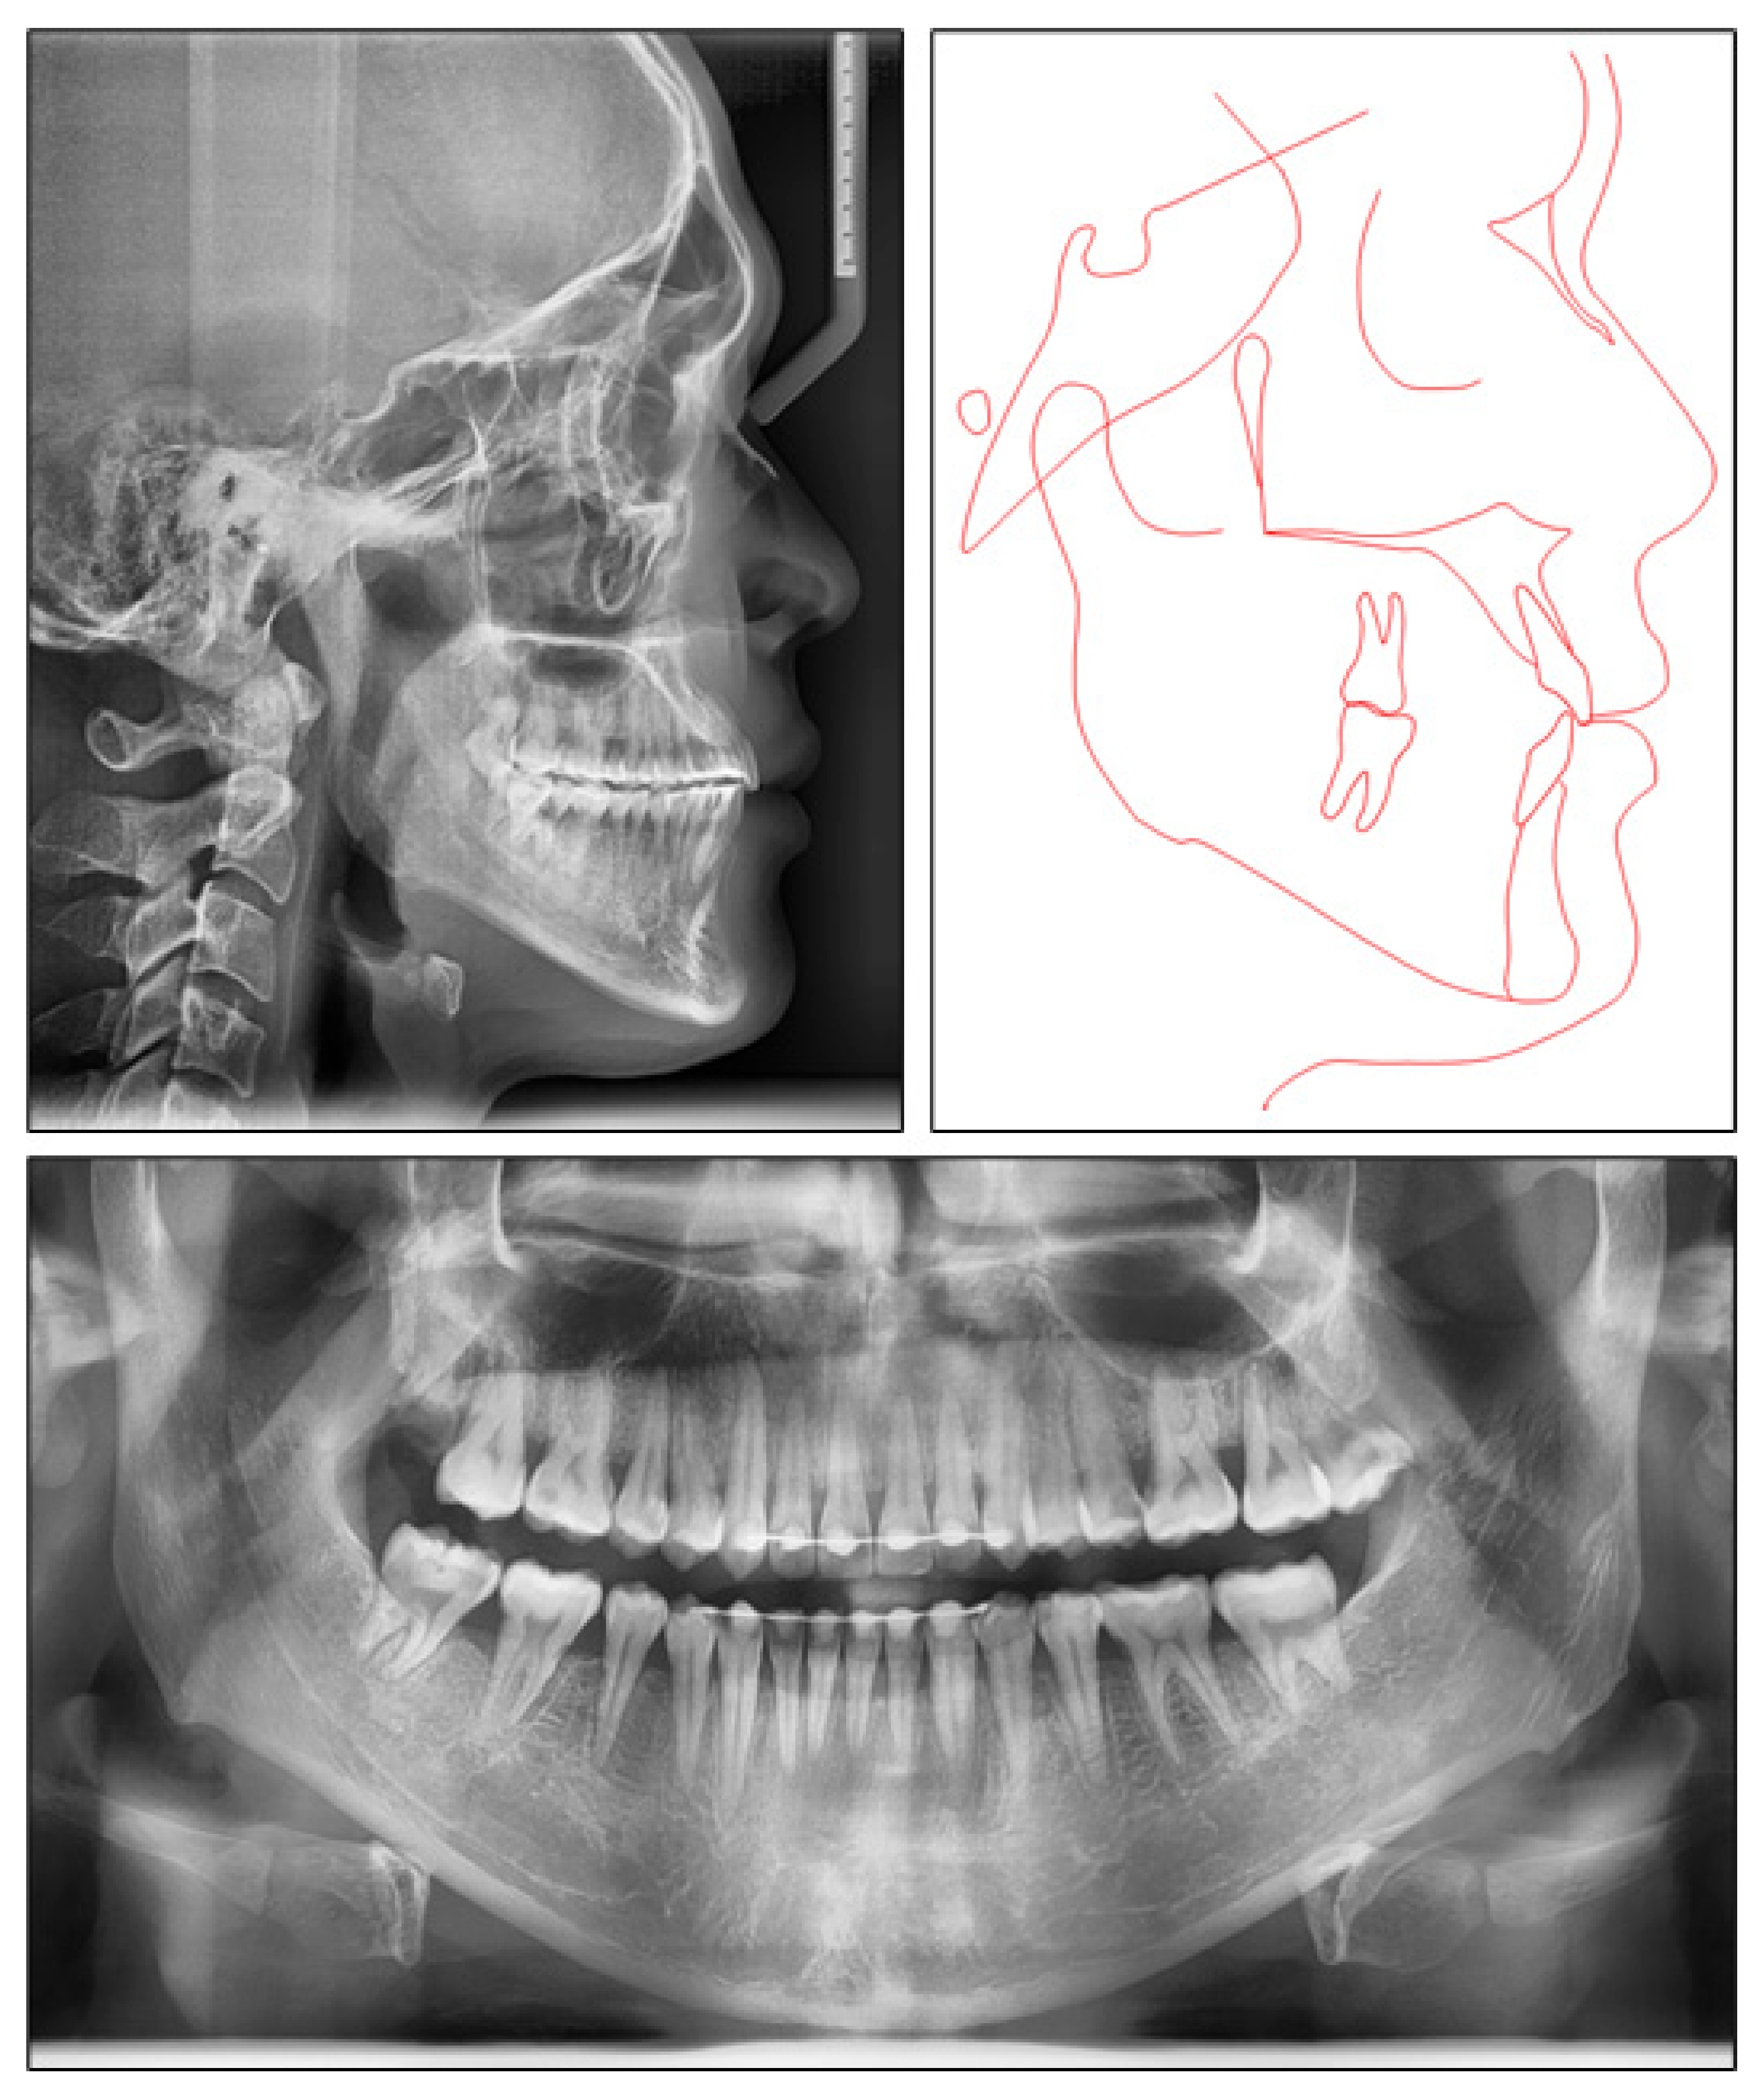

2.1. Diagnosis and Etiology